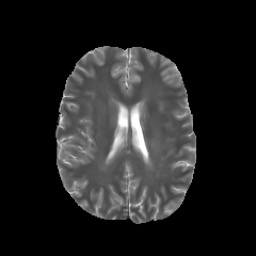

Denoising diffusion probabilistic models (DDPMs) have achieved unprecedented success in computer vision. However, they remain underutilized in medical imaging, a field crucial for disease diagnosis and treatment planning. This is primarily due to the high computational cost associated with (1) the use of large number of time steps (e.g., 1,000) in diffusion processes and (2) the increased dimensionality of medical images, which are often 3D or 4D. Training a diffusion model on medical images typically takes days to weeks, while sampling each image volume takes minutes to hours. To address this challenge, we introduce Fast-DDPM, a simple yet effective approach capable of improving training speed, sampling speed, and generation quality simultaneously. Unlike DDPM, which trains the image denoiser across 1,000 time steps, Fast-DDPM trains and samples using only 10 time steps. The key to our method lies in aligning the training and sampling procedures. We introduced two efficient noise schedulers with 10 time steps: one with uniform time step sampling and another with non-uniform sampling. We evaluated Fast-DDPM across three medical image-to-image generation tasks: multi-image super-resolution, image denoising, and image-to-image translation. Fast-DDPM outperformed DDPM and current state-of-the-art methods based on convolutional networks and generative adversarial networks in all tasks. Additionally, Fast-DDPM reduced training time by a factor of 5 and sampling time by a factor of 100 compared to DDPM. Our code is publicly available at: https://github.com/mirthAI/Fast-DDPM.